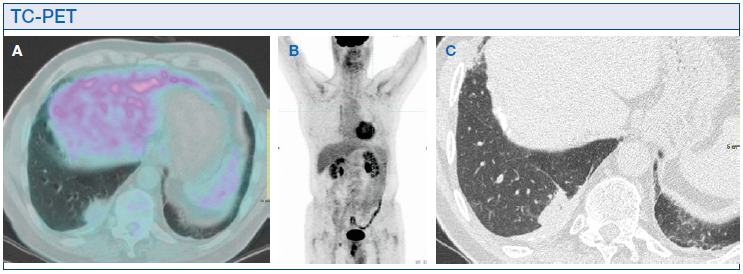

L’ulteriore indagine radiologica che ha confermato tale ipotesi diagnostica, evitando il ricorso ad indagini invasive, è la TC-PET. Essa ha dimostrato assenza di segni di attività metabolica sia a livello delle placche pleuriche sia del nodulo nel lobo inferiore destro (Figura 2A). Assenza di captazione patologica anche a livello delle stazioni linfonodali ilo-mediastiniche o in altri distretti corporei (Figura 2B).

In presenza di un quadro TC tipico e con TC-PET negativa, molti Autori concordano nell’evitare interventi invasivi, bioptici o escissionali. È consigliato il follow-up TC, come realizzato nel caso del nostro paziente, che ha dimostrato la stazionarietà del quadro anche dopo 5 anni (Figura 2C).